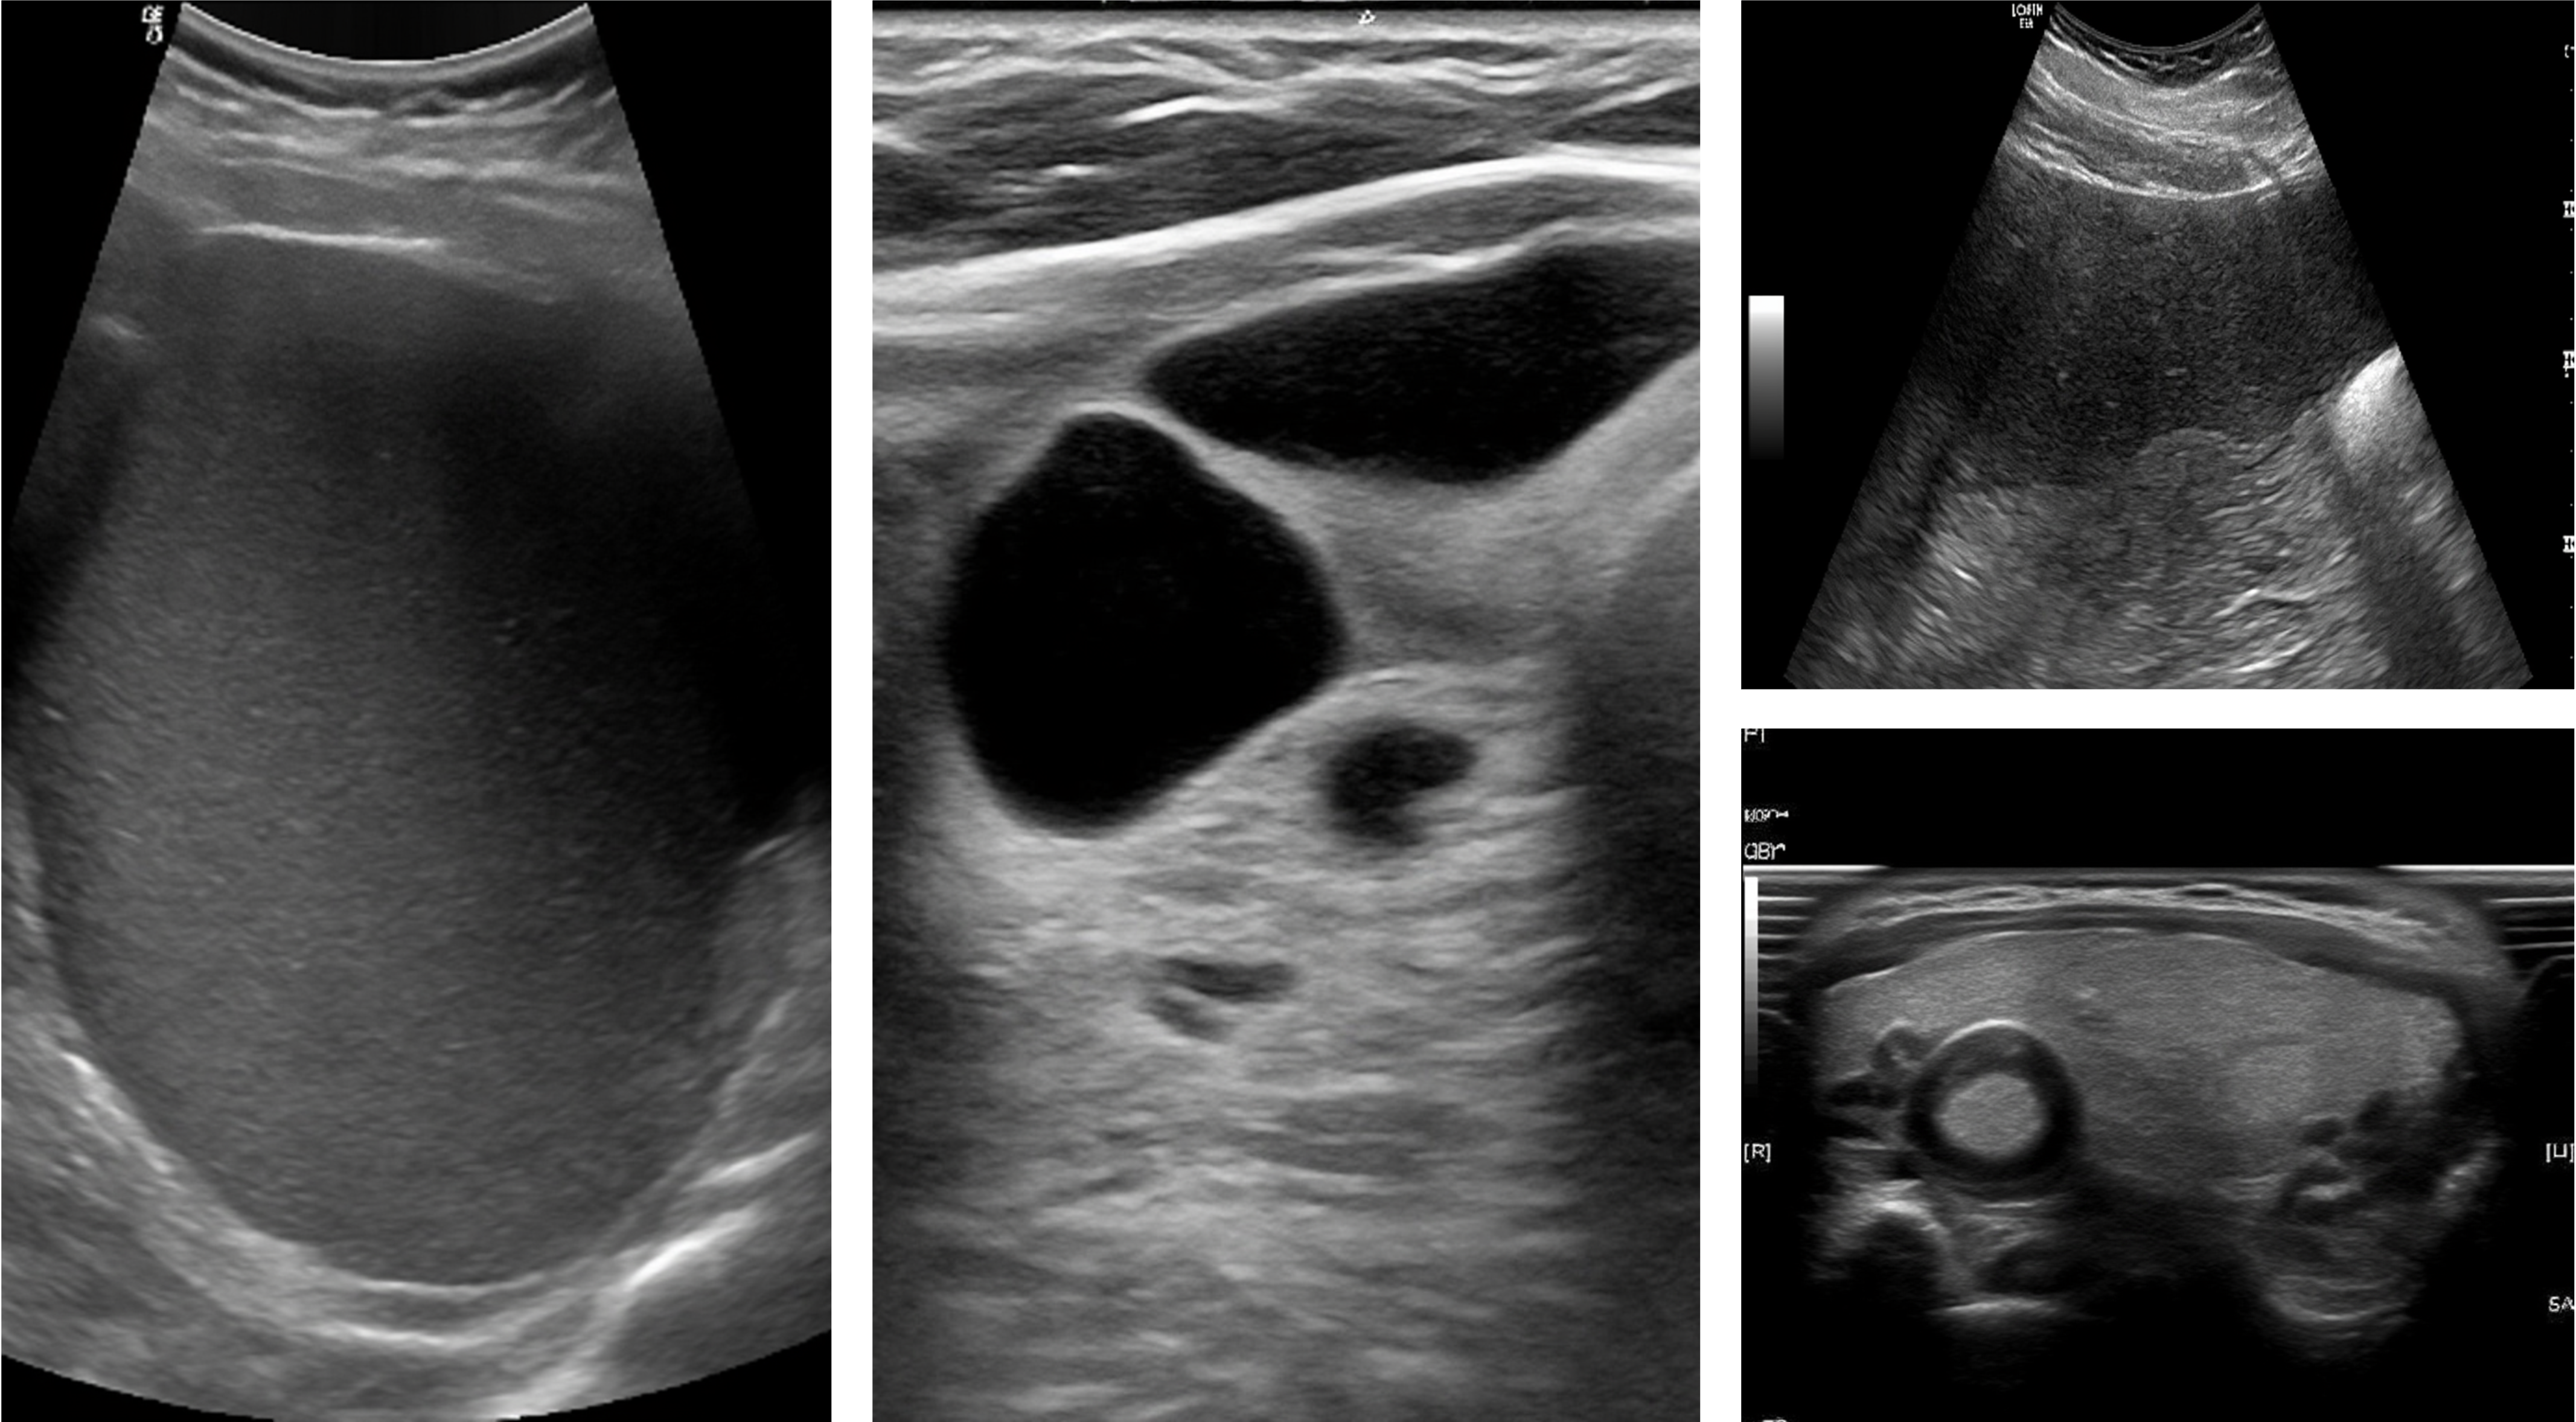

Ultrasound